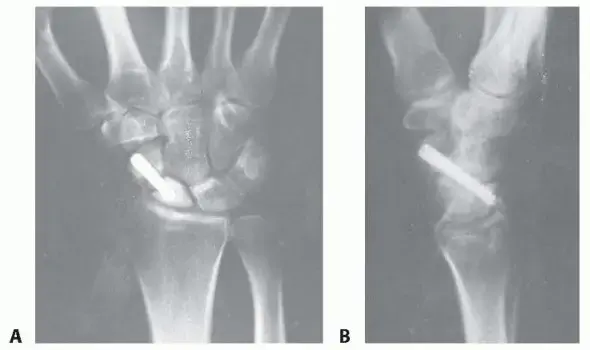

• أ. استئصال جزء من العظم الزورقي (Partial Scaphoid Excision):

هذا هو الإجراء الذي نركز عليه في هذا الدليل، وهو خيار فعال ومهم في حالات مختارة.

• متى يُختار؟ يُلجأ إليه عندما يكون هناك جزء من العظم الزورقي غير حيوي (ميت) أو مشوه، ويسبب ألمًا شديدًا، خاصة في القطب القريب من العظم، أو عندما تكون هناك علامات مبكرة لالتهاب المفاصل. الهدف الرئيسي هو إزالة مصدر الألم والمحافظة على أكبر قدر ممكن من وظيفة الرسغ.

• كيف يتم الإجراء؟ يقوم الجراح بإزالة الجزء المتضرر أو غير القابل للالتئام من العظم الزورقي. يمكن أن يكون هذا الجزء هو القطب القريب الذي يعاني من ضعف في التروية الدموية، أو أي جزء آخر مسبب للألم والتدهور.

• الهدف: تخفيف الألم، إبطاء أو منع تطور التهاب المفاصل، وتحسين مدى حركة الرسغ. لا يهدف إلى التئام العظم بالكامل، بل إلى "إنقاذ" الرسغ من التدهور المستمر.

• مرشحون لهذا الإجراء: المرضى الذين يعانون من ألم مزمن بسبب عدم التئام العظم الزورقي، خاصة في القطب القريب، والذين فشلوا في الالتئام بعد محاولة واحدة أو أكثر من جراحات التثبيت الداخلي مع ترقيع العظام، والذين ليس لديهم تآكل مفصلي واسع النطاق (التهاب مفاصل متقدم).